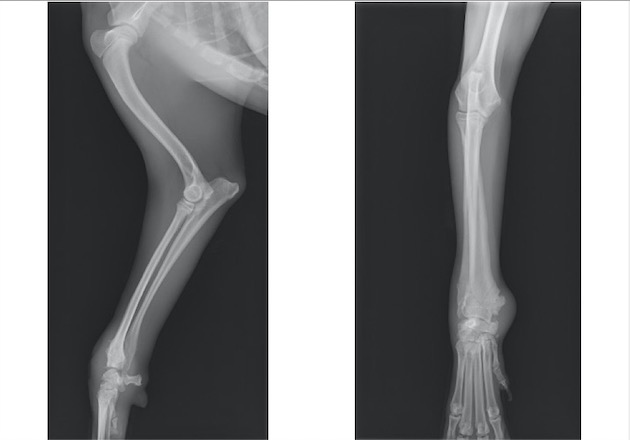

トイプードル 雌 3ヵ月齢

ソファーの背もたれから落下後、右前肢居城を主訴に来院。

視診上、両前肢の明らかな左右差は認められませんでしたが、触診検査において肘関節における圧痛を確認しました。

単純X線検査を実施したところ、上腕骨遠位外顆骨折が認められ、上腕骨遠位の成長板をまたぐ骨折であったことから成長板骨折(Salter-Haris Type4)と診断して外科的処置を実施しました。

背掌像より上腕骨遠位外顆の骨折が認められました。